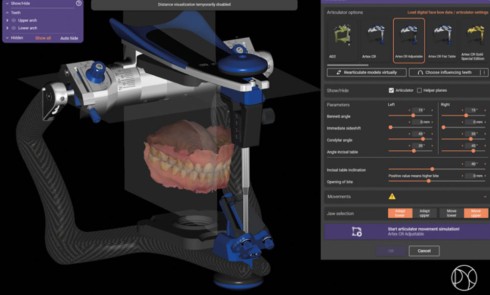

Le rythme effréné et l’obligation de performance qui caractérisent notre époque engendrent des tensions, du stress, qui à leur tour...À propos d’un cas clinique multidisciplinaire en zone esthétique